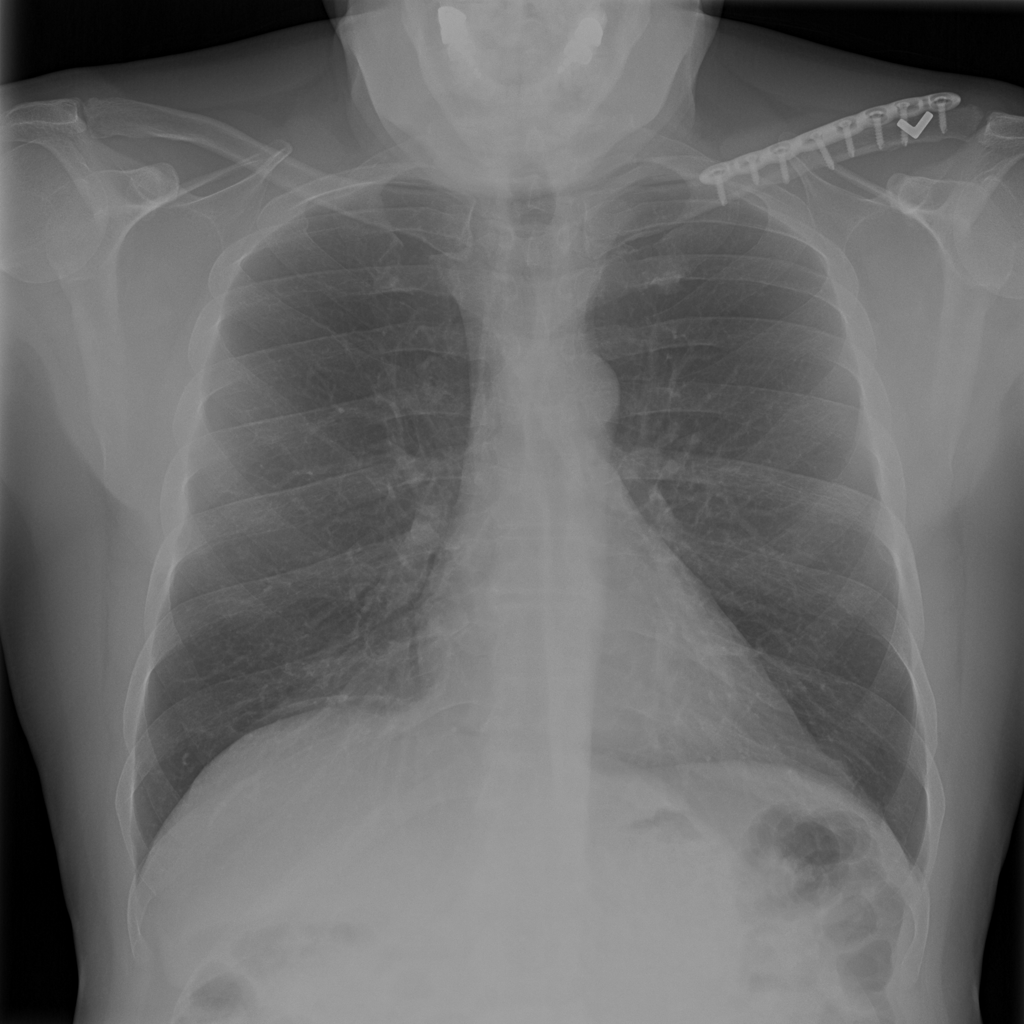

PAT-86C8 · IMG-006Atelectasis

PAT-86C8 · IMG-006

PA